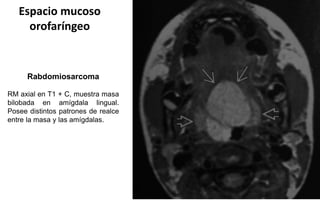

Espacio mucoso

orofaríngeo

Rabdomiosarcoma

RM axial en T1 + C, muestra masa

bilobada en amígdala lingual.

Posee distintos patrones de realce

entre la masa y las amígdalas.